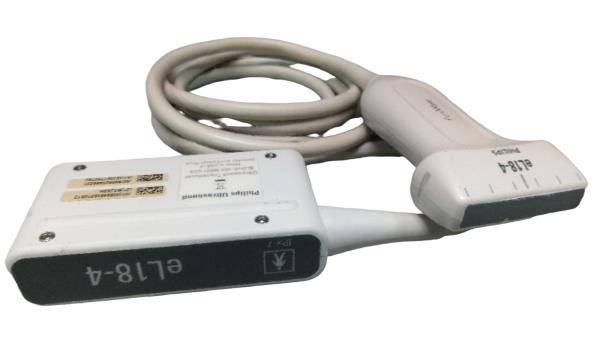

Probe Function: 3.5MHZ convex, abdominal organs

This ultrasound scanner's dual probe system means that healthcare providers can easily switch between imaging modes. The convex probe is excellent for abdominal and fetal imaging, while the transvaginal probe allows for detailed pelvic examinations. Because of this flexibility, medical professionals can perform a wide variety of procedures without needing multiple machines. Therefore, hospitals can optimize their workflow and save valuable time.